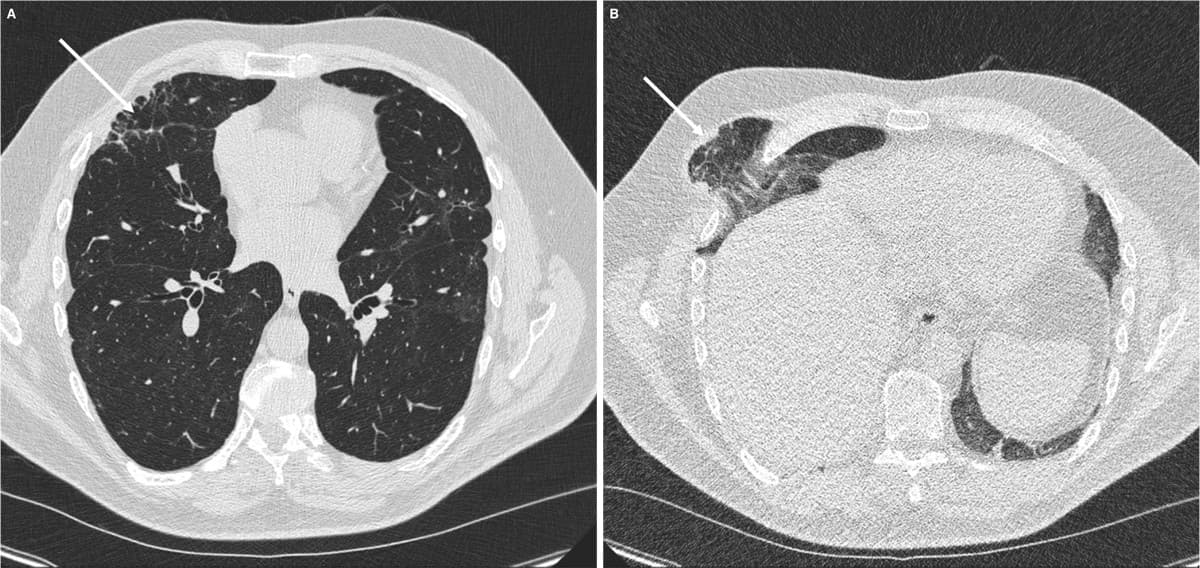

Som led i udredningen af interstitiel lungesygdom blev der foretaget en ny HRCT. I inspirationsfasen sås stationære forhold i de fibrotiske forandringer anteriort samt post-COVID-19-matglastegning, som også var kendt fra tidligere (A). I eksspirationsfasen visualiseredes en tidligere uerkendt herniering af højre over- og mellemlap fortil mellem costa 3 og costa 4 (B).

Defekten i thoraxvæggen var sequelae efter torakotomi i forbindelse med mitralplastik. Patienten havde gennem mange år bemærket en smertefri frembuling ved hoste. Han blev henvist til thoraxkirurgisk vurdering, hvor man afstod fra operation.

Lungehernie er en sjælden komplikation til torakotomi [1, 2] og kan give fokal lungefibrose formentlig pga. gentagne traumer mod lungevævet. Herniet hos den 56-årige var ikke tidligere erkendt trods flere HRCT i eksspirationsfase. Ved mistanke om lungehernie anbefales derfor CT under Valsalvas manøvre [3].